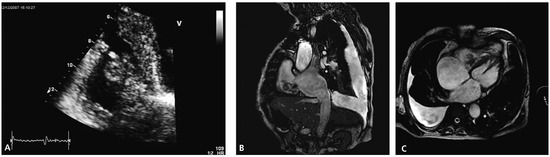

Percutaneous Implantation of an ASD Occluder with Intracardiac Ultrasound

by Frank Enseleit, Oliver Kretschmar and Thomas F. Lüscher

Cardiovasc. Med. 2010, 13(9), 290; https://doi.org/10.4414/cvm.2010.01522 - 15 Sep 2010

A 52-year-old female was admitted for further evaluation of a continuous heart murmur. Transthoracic echocardiography revealed a secundum type atrial septal defect (ASD II) with a size of 13 × 16 mm and considerable left-to-right shunt (Qp/Qs = 2), as well as elevated [...] Read more.

A 52-year-old female was admitted for further evaluation of a continuous heart murmur. Transthoracic echocardiography revealed a secundum type atrial septal defect (ASD II) with a size of 13 × 16 mm and considerable left-to-right shunt (Qp/Qs = 2), as well as elevated pulmonary artery pressure (RV/RA pressure gradient = 38 mm Hg) [...] Full article